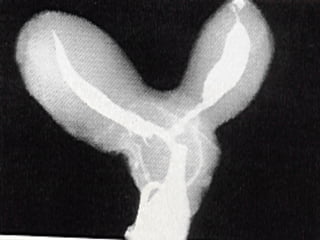

• 12.

Congenital Uterine Anomaly n Diagnosis: History Pelvic exam Hysterosalpingography U/S MRI Laproscopy Hysteroscopy IVP or U/S (Exclude Renal anomaly )

Congenital Uterine Anomaly

n  Treatment:

1- Double uterus (didelphic uterus): no need to treat.

2- Bicornate ut. --------- Strassmann procedure

( if indicated )

3- Ut. Septum --------- (BCP for dysmenorrhea ),

Tompkins metroplasty or Hysteroscopic resection of

septum )

4- Unicornate ut. -------- Surgery indicated if there is

blind horn which cause symptom----- surgical resection

of blind horn.